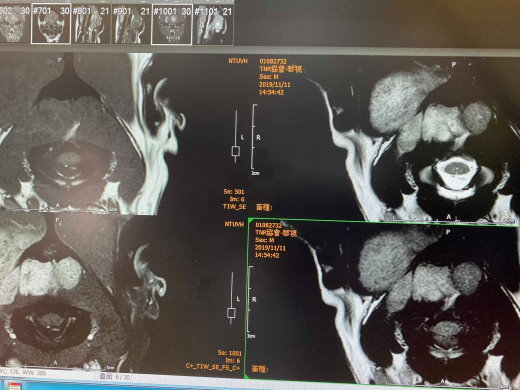

做核磁共振、外加電腦斷層。

發現腦部長腫瘤、且已侵蝕掉大片骨頭,

腦部手術在人類也是非常困難大刀,

思及腫瘤已過大、狗狗也年邁,